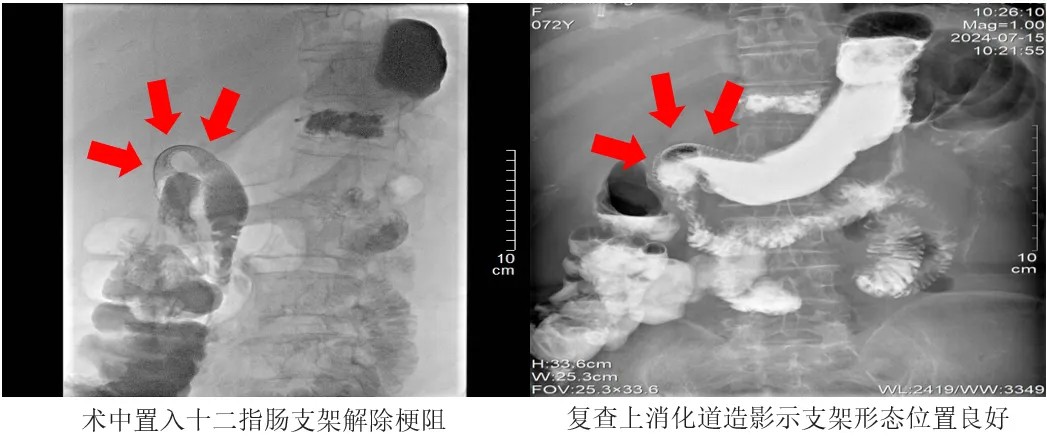

術中,醫生拔除胃腸減壓管,隨后通過王阿姨口腔,利用導管與導絲配合,精準進行了幽門插管操作,并成功穿越了狹窄區域。緊接著,他們沿著導絲順利放置了一枚十二指腸支架,且在透視下確認了支架的位置完全符合要求。

整個手術過程僅耗時35分鐘。

術后24小時,王阿姨開始喝水。術后48小時,王阿姨開始進食米湯等流質食物。術后72小時,王阿姨進食蛋羹、爛面條等半流質食物。復查上消化道造影顯示,支架形態、位置均良好,術區未見明顯狹窄及滲漏。王阿姨恢復了正常飲食。